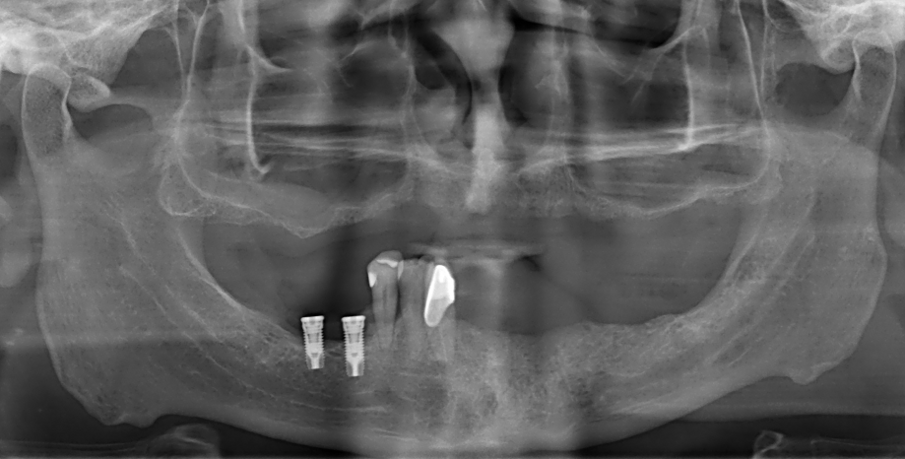

Un paziente maschio di 58 anni (Fig. 1), senza anamnesi medica rilevante, si presenta alla nostra attenzione richiedendo una riabilitazione protesica fissa su impianti alle due arcate. L’edentulia e l’atrofia ossea all’arcata superiore, come verosimile risultato di parodontite cronica dell’adulto, e la presenza di tre denti e due impianti con una prognosi parodontale infausta, sono evidenti all’esame clinico e nelle immagini radiologiche (Fig. 2), così com’è visibile l’incongruenza delle protesi rimovibili, con estetica compromessa e malocclusione in cross bite monolaterale (Fig. 3), con segni e sintomi disfunzionali.

Dopo la rimozione dei denti residui e degli impianti, il paziente è stato immediatamente riabilitato con due protesi totali rimovibili diagnostiche in RP, che hanno migliorato i rapporti intermascellari, la VDO, OB, OJ, fonetica ed estetica. È stato eseguito un tracciato cefalometrico su una radiografia laterale del cranio per una valutazione funzionale iniziale del caso, seguita da una pianificazione protesica virtuale (Fig. 4), quindi radiologica (Fig. 5) e chirurgica. Le caratteristiche delle protesi studiate hanno determinato la pianificazione chirurgica (Smop, SwissMeda) (Fig. 6) e due guide chirurgiche sono state successivamente sinterizzate al laser (2Ingis) (Fig. 7). Gli impianti sono stati quindi posizionati come programmato (Figg. 8, 9), ad eccezione di quelli ai mascellari posteriori, dove è stato eseguito bilateralmente un grande rialzo del seno mascellare (Fig. 10).